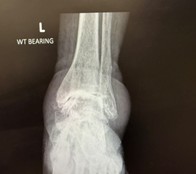

The latest data shows that ankle replacement survivorship and patient outcomes have improved significantly in recent years.

With modern implants, better surgical techniques, and refined rehabilitation pathways, patients are achieving excellent long-term mobility and comfort.

For others with more advanced arthritis, today’s ankle replacement techniques can restore movement and reduce pain while keeping the joint flexible something fusion can’t offer.